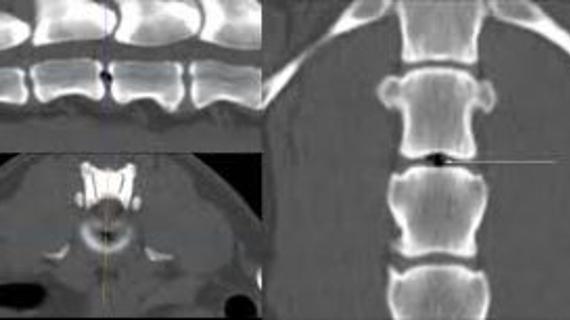

Как отличить остеохондроз от рака позвоночника? Сделать это может только врач на основе ряда исследований. Самостоятельно можно попытаться дифференцировать эти два заболевания по...